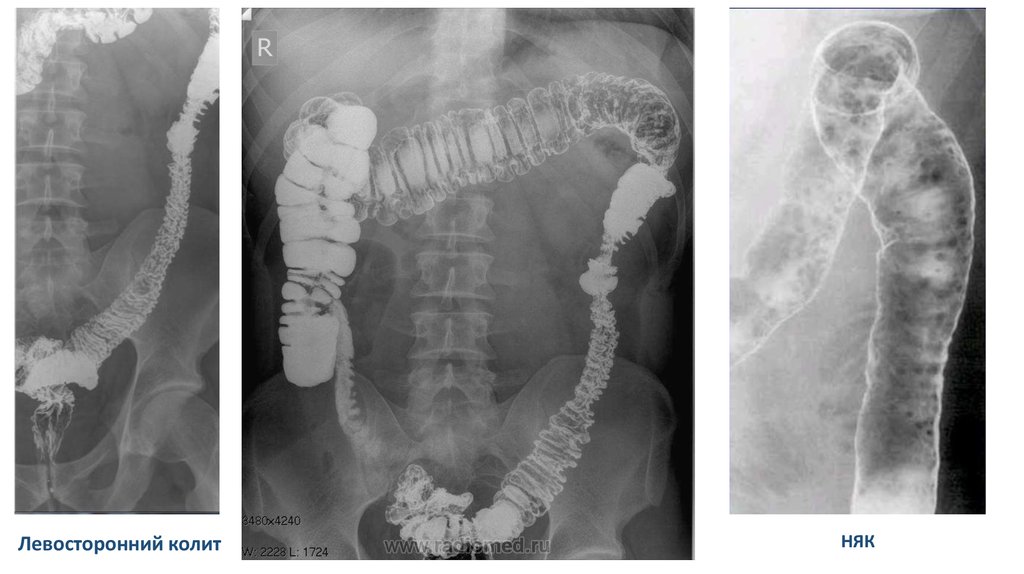

Левосторонний колит

НЯК